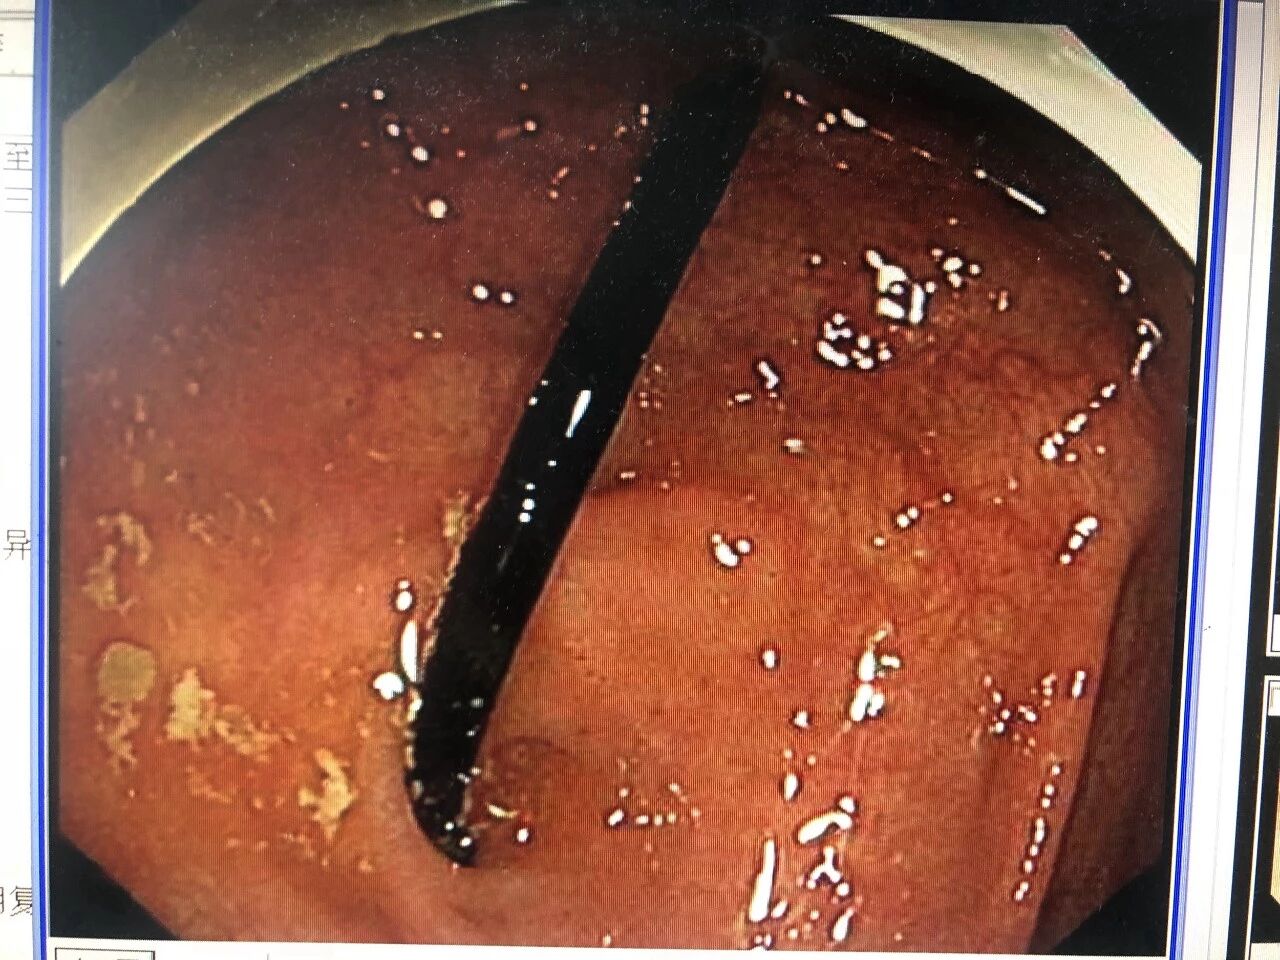

胃镜检查

没有发现钉子

通过前期的肠道准备,5月14日,杨伟兴再次安排罗锋做了腹部CT检查,结果提示钉子已经滑落至回盲部。时机正好,杨伟兴立即准备为罗锋做急诊结肠镜检查。

10分钟后,杨伟兴从罗锋回盲部顺利取出一根35mm的钉子。而此时距离罗锋误吞钉子已过去了43个小时。